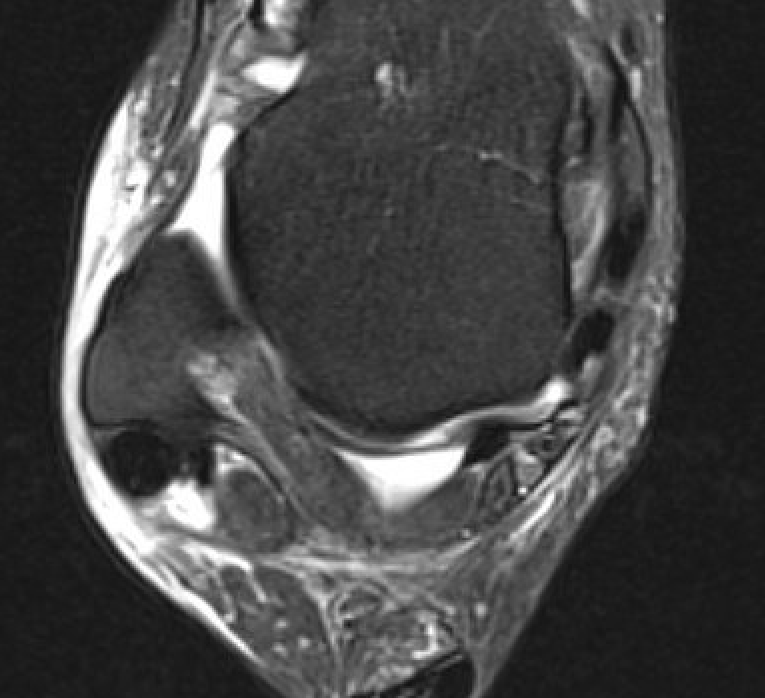

- tears

Peroneal brevis tears